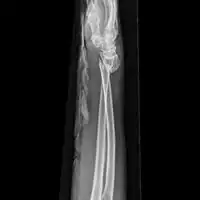

| Midshaft fracture of the radius and ulna | |

A forearm fracture refers to one or more breaks of the bones in the forearm; a radius fracture or ulna fracture, or more commonly both.[3][6] The bones can break in several places; near the wrist, in the middle or near the elbow.[7] When both bones break, the breaks occur at around the same level.[6] The fractures can be closed, with skin intact, or open, where there is accompanying overlying wound, and are often associated with wrist or elbow joint damage such as dislocation or displacement.[4][1]